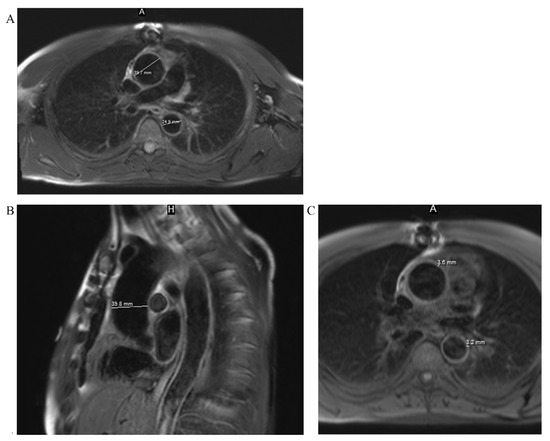

Moreover, aortic magnetic resonance imaging (MRI) was performed to measure diameters of entire thoracic aorta and for the assessment of aortic wall morphology. Thickened walls (3–3.6 mm) of the ascending and descending parts of aorta were noted. Subsequent parameters of thoracic aorta were obtained: aortic annulus, 22 mm (3-chamber view); aortic sinuses, 35 mm (3-chamber view); ascending aorta in the proximal and middle, 1/3 40 mm; distal, 1/3 39 mm; aortic arch in the T1 segment, 33 mm; T2 segment, 28 mm; and descending aorta, 25 mm (Fig. 5).

Fig. 5. - MRI views. A, a dilatation of the ascending part of the aorta in T2W FS axial view; B, a dilatation of the ascending part of the aorta in T2W FS sagittal view; C, thickened walls of the ascending and descending parts of the aorta in T1W FS axial view.